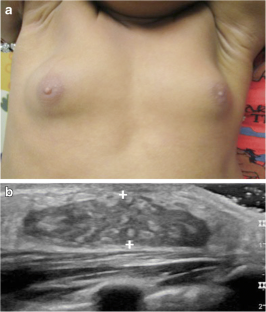

de Vries L, Horev G, Schwartz M, Phillip M (2006) Ultrasonographic and clinical parameters for early differentiation between precocious puberty and premature thelarche. Eur J Endocrinol 154:891–898

Youn I, Park SH, Lim IS, Kim SJ (2015) Ultrasound assessment of breast development: distinction between premature thelarche and precocious puberty. AJR Am J Roentgenol 204:620–624